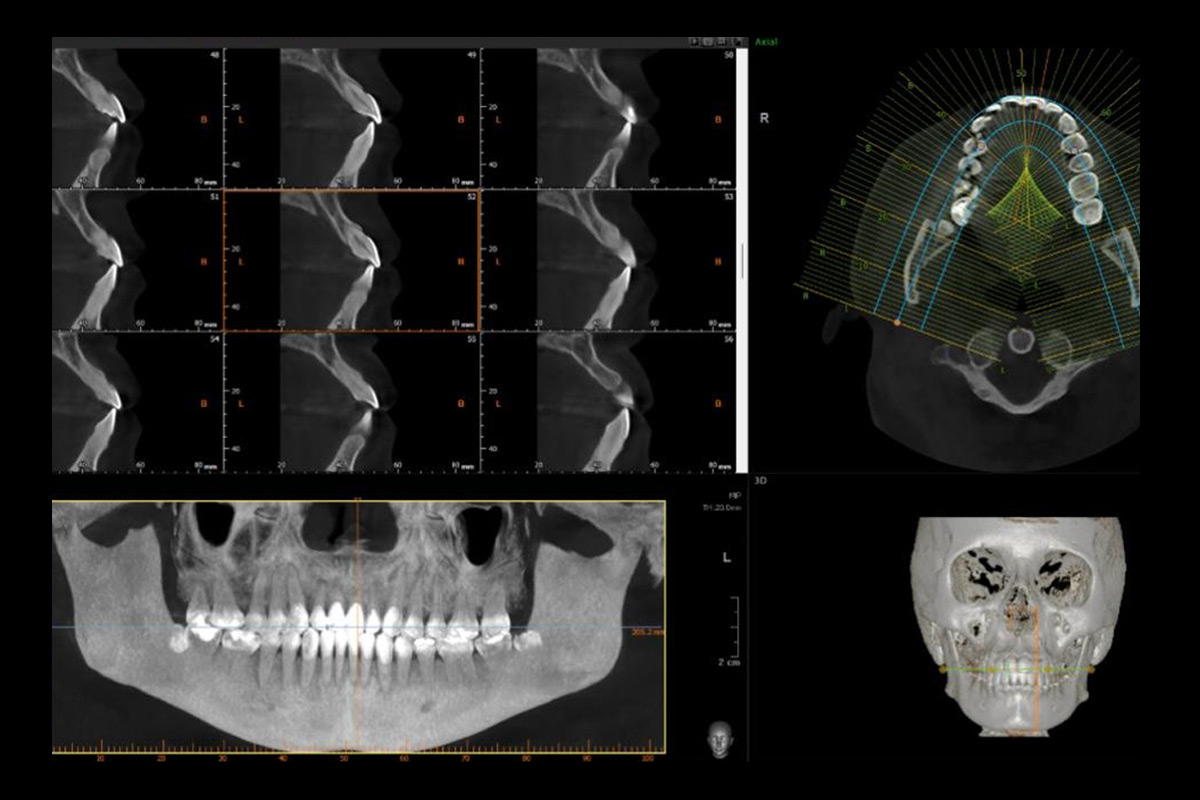

La Interpretación Tomográfica es un servicio especializado que se enfoca en el análisis detallado y la interpretación de imágenes tomográficas obtenidas mediante tecnología avanzada, como la tomografía computarizada de haz cónico (CBCT). Este servicio es crucial para un diagnóstico preciso y la planificación efectiva de tratamientos en odontología, cirugía maxilofacial y otras especialidades médicas que requieren una visión clara y detallada de las estructuras anatómicas.

Los especialistas en interpretación tomográfica revisan estas imágenes para identificar cualquier anomalía, como fracturas, quistes, tumores, malformaciones, o la posición exacta de dientes y raíces. Este análisis es fundamental para determinar el diagnóstico adecuado y para guiar la planificación de tratamientos complejos, como cirugías, colocación de implantes o tratamientos de ortodoncia.

Implantología: La interpretación tomográfica es crucial para la colocación precisa de implantes dentales, asegurando que se eviten estructuras críticas como nervios y senos maxilares, y optimizando el ajuste y la integración del implante en el hueso.

Cirugía Maxilofacial: Es fundamental en la planificación de cirugías ortognáticas y otras intervenciones complejas, permitiendo a los cirujanos planificar y simular procedimientos antes de la operación, lo que mejora la precisión y reduce los riesgos.

Ortodoncia: En ortodoncia, ayuda a evaluar la relación entre los dientes y las estructuras óseas, facilitando la planificación de movimientos dentales y el diseño de aparatos ortodónticos personalizados.

Endodoncia Avanzada: Permite la localización exacta de canales radiculares complejos y la identificación de patologías que podrían no ser visibles en radiografías convencionales.

Detección de Patologías: La interpretación tomográfica es esencial para la identificación temprana de tumores, quistes y otras anomalías que podrían requerir intervención quirúrgica o tratamiento específico.